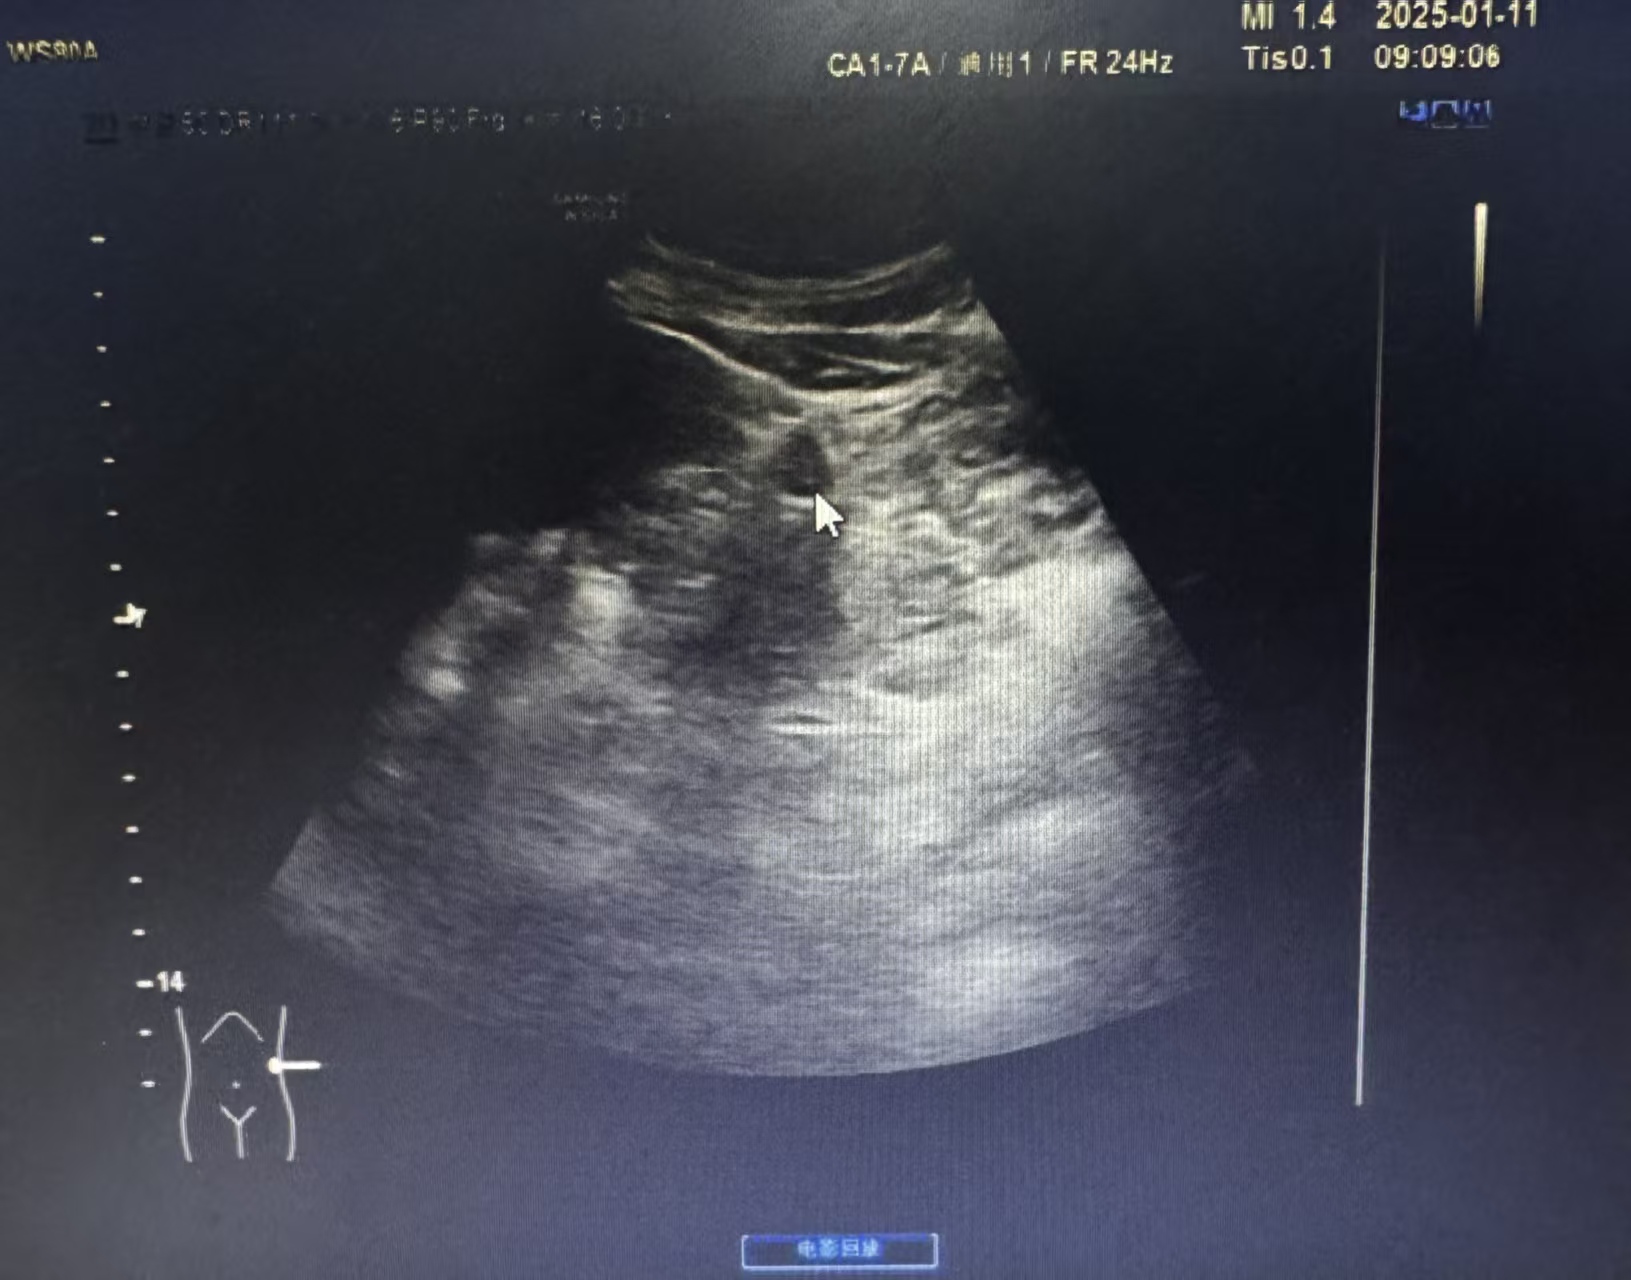

超声眼里的“小间谍”长啥样?

做超声检查时,副脾逃不过医生的“火眼金睛”。它通常有几个明显特征:

1. 位置固定

最爱躲在脾脏的“家门口”,也就是脾门附近,像个忠诚的小跟班。偶尔也会跑到胰尾附近。

2. 外形圆润

大多呈边界清晰的圆形或椭圆形,直径通常在1-2厘米,像个光滑的小球。

3. 善于伪装

这点最关键!在超声图像上,副脾的回声质地和主脾脏一模一样。这就是判断它是副脾而非其他肿物的核心依据。